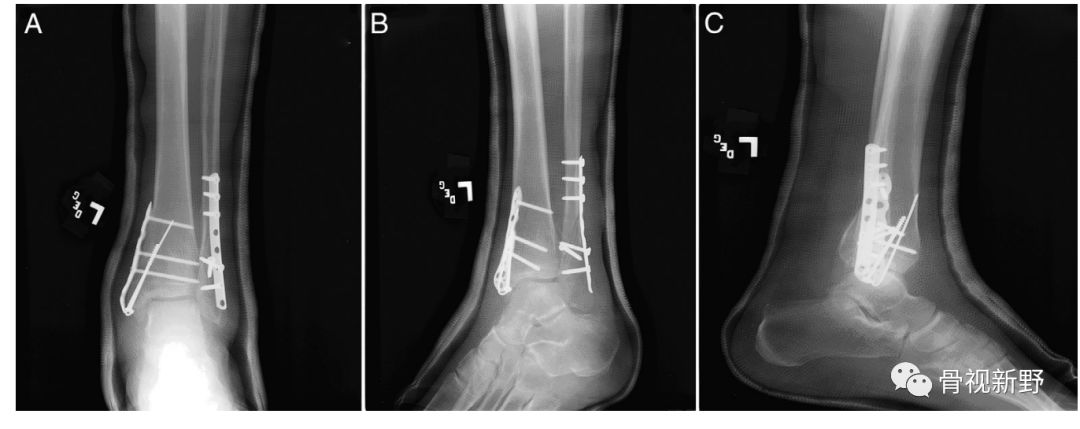

内踝垂直型骨折的buttress固定

内踝骨折根据骨折线走形方向可分为:横形、斜形、粉碎、垂直骨折,其中斜形、垂直形,特别是垂直型骨折的剪力较大,常规克氏针、空心钉、张力带等固定措施不能很好中和剪切力,应用buttress钢板的防滑原理可减少不愈合及畸形愈的并发症。

内踝斜形骨折—腓骨远端锁定钢板防滑固定(J Foot Ankle Surg. 2015 ;54(6):1202-5.)

腓骨远端锁定板防滑+克氏针防旋固定

锁定重建板单皮质固定防滑+空心钉加压固定